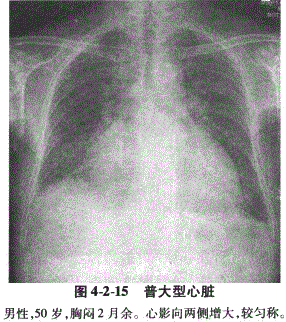

3.普大型:常见于全心心肌损害、大量心包积液和风湿性多瓣膜损害。心影向两侧增大,多较匀称,肺动脉段平直,主动脉结多正常(图4-2-15)。